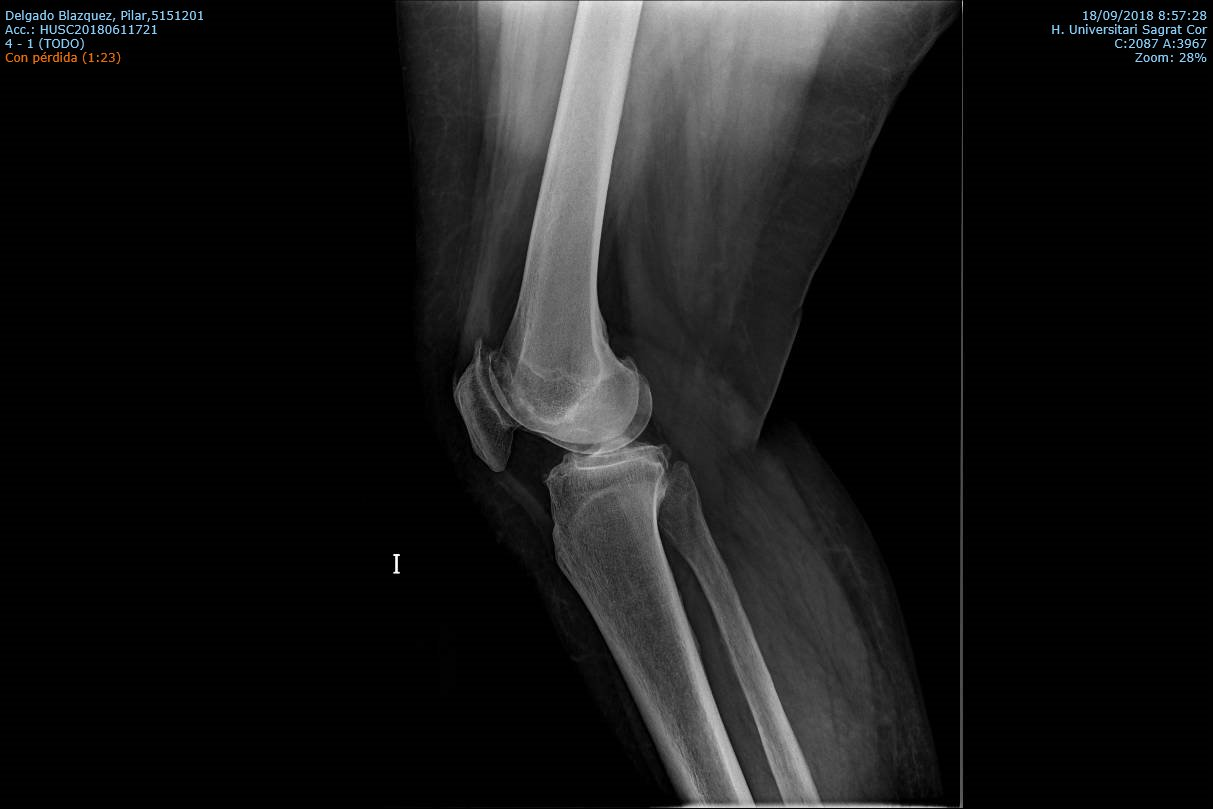

Diagnostico

Los estudios previos para el diagnostico de una artrosis de rodilla son principalmente un examen clínico del médico y las radiografías. El examen medico habitualmente confirma dolor en la parte medial, anterior y lateral de rodilla, rigidez con reducción en el rango de movimiento, crepitación o roce con el movimiento de la rodilla y cojera durante la marcha. En la radiografía típicamente se observa los cambios en la forma del hueso y cartílago como la pérdida de grosor, deformación y endurecimiento. Ocasionalmente para confirmar el diagnóstico de la patología de un compartimiento o de una fase muy inicial, se puede usar otras pruebas de imagen como la resonancia magnética, tomografía computarizada (TC) o gammagrafía ósea que valora mejor las partes blandas alrededor de la articulación.